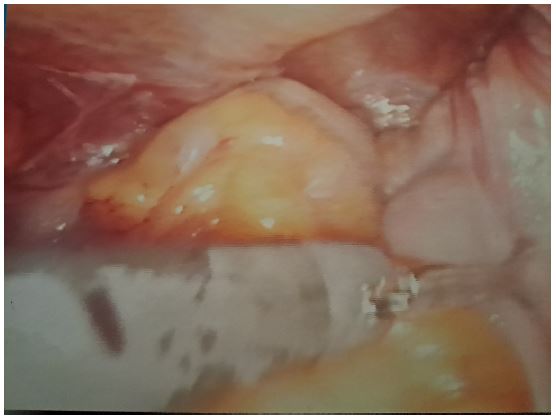

Figure 4: Hernia sac.

Laparoscopy was performed in general anaesthesia, accessed the retroperitoneal area, de-prepared hernial sack, and closed the muscular defect with PTFE screen. Operative surgery was concluded with the reparation of peritoneum (Figures 3-5).